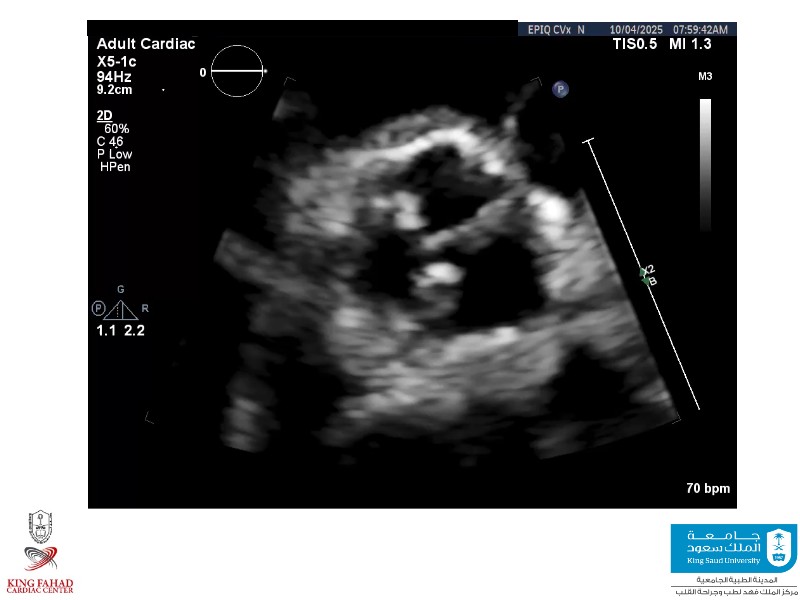

Second valve strategies with SAPIEN 3 Ultra RESILIA

This session helps you anticipate and address complex scenarios such as mitral valve-in-valve, TAV-in-SAV, and valve-in-valve-in-valve procedures. Learn from expert case discussions that explore procedural strategies, technical challenges, and best practices to optimize outcomes in redo structural heart interventions.

- To anticipate and manage second valve scenarios with SAPIEN 3 Ultra RESILIA, including mitral valve-in-valve, TAV-in-SAV, and TAV-in-TAV